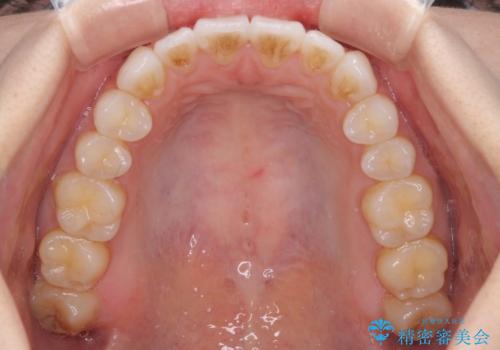

- 矯正治療の後戻りを気にして来院された患者様です。

後戻りは軽微でしたが、舌突出癖が認められ、初診時には上下前歯に舌がはまるスペースができていました。

舌突出癖の改善を行いながら、インビザライン・ライトにより矯正治療を行うこととしました。

舌突出癖の改善により上下前歯が接触するようになり、前歯でものを咬みきる必要のある食事がスムーズに行えるようになりました。